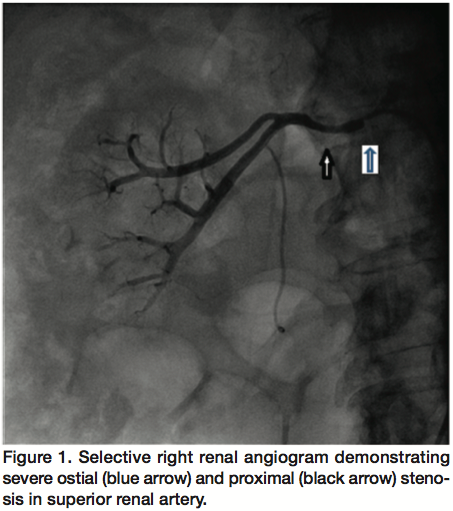

Selective renal arteriography revealed a solitary left renal artery with mild stenosis. However, the right kidney had a dual arterial supply, superior and inferior right renal arteries. Ostia of the 2 renal arteries were very close, but selective arteriography could not be performed using one catheter at a time, and each one had to be engaged separately. Both the superior (Figure 1) and inferior (Figure 2) renal arteries had an ostial 95% stenosis, with a pressure gradient of 70 mm Hg. Each artery supplied almost half the kidney, and there was no true “dominant” artery. Interestingly, the 2 ostia were too close to allow for simultaneous engagement even using 2 catheters.